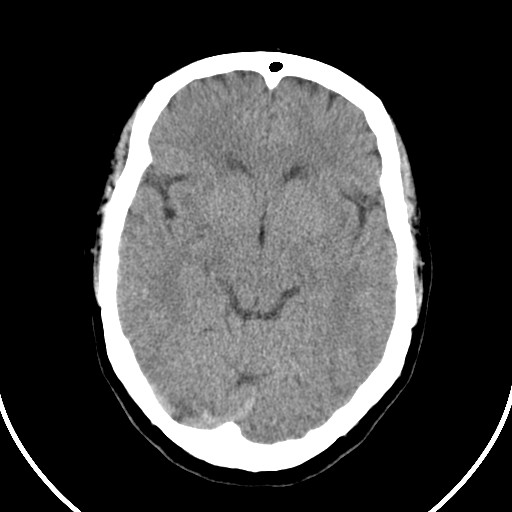

标题: CT21850:女,56岁,右中指淤肿,右手麻痹1天

女,56岁,右中指淤肿,右手麻痹1天

右枕叶低密度区伴硬膜下血肿——增强扫描或mri。

双侧侧脑室额角旁对称性略低密度影,边缘模糊,无占位效应,考虑轻度脑白质稀疏症(病人有高血压吗).,右枕叶低密度影多为伪影,不放心薄扫一下.

右枕叶条状低密度影不应该忽略可能极具意义